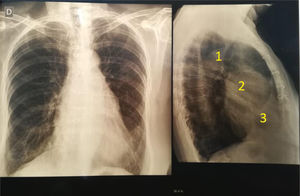

Paciente femenina de 64 años con antecedente de dos cirugías previas, una por ductus arterioso a los 12 años y otra por una ventana aortopulmonar a los 16 años. Se encontraba asintomática. En el examen físico cardiovascular, se detectaron ruidos cardiacos rítmicos, normofonéticos, sin edemas, ni disnea. El electrocardiograma mostró ritmo sinusal a 80 lpm, con signos de hipertrofia ventricular. En la radiografía de tórax, en la proyección frente, no se observan anormalidades con un índice cardiotorácico conservado y alambres de cirugía previa. En el perfil, aparece un gran aneurisma de raíz aórtica (fig. 1).